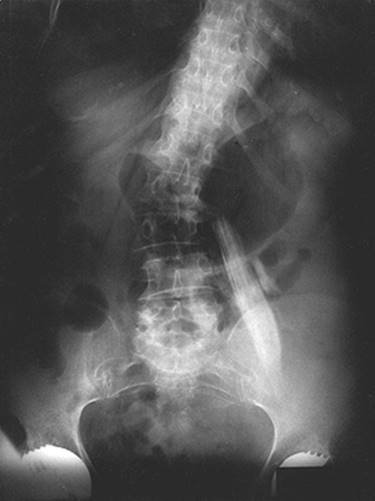

Figure 13-2. X-ray indicating appropriate positioning.